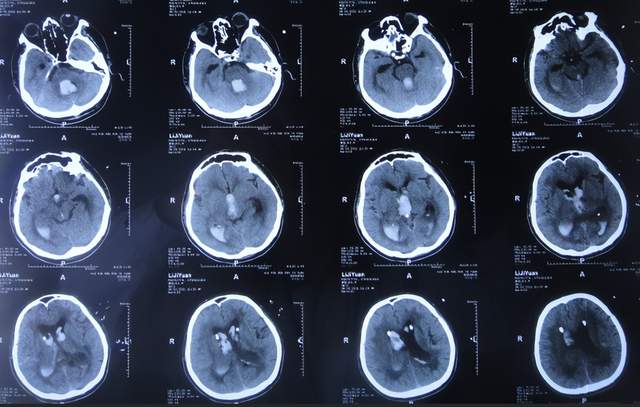

腰大池引流术后4天即2021年9月12日,查头颅CT示脑室内积血基本消失(图-5)。

图-5:2021年9月12日头颅CT

腰大池引流术后8天即2021年9月20日,给予拔除腰大池引流管,之后给予保守治疗。

拔除腰大池引流管后3天即2021年9月23日,查头颅CT示(图-6)后继续给予保守治疗。

图-6:2021年9月23日头颅CT

腰大池引流管拔除后13天即2021年10月3日,患者恢复至可以搀扶下行走约20米,能简单言语,查头颅CT较2021年9月23日认为没有明显变化(图-7)。

图-7:2021年10月3日头颅CT

但继续保留治疗20余天的时间内,患者逐渐出现意识变差,走路变差,至2021年11月3日(腰大池引流管拔除后31天),病情变重致不能走路,不能言语,查头颅CT(图-8)后考虑脑积水,给予腰椎穿刺治疗。

图-8:2021年11月3日头颅CT

但腰椎穿刺治疗7天病情无明显改善,于2021年11月10日(住院治疗2月余)出院回家休养,出院时头颅CT示仍有脑积水(图-9);出院时:意识差,不能走路,不能言语。

图-9:2021年11月10日头颅CT